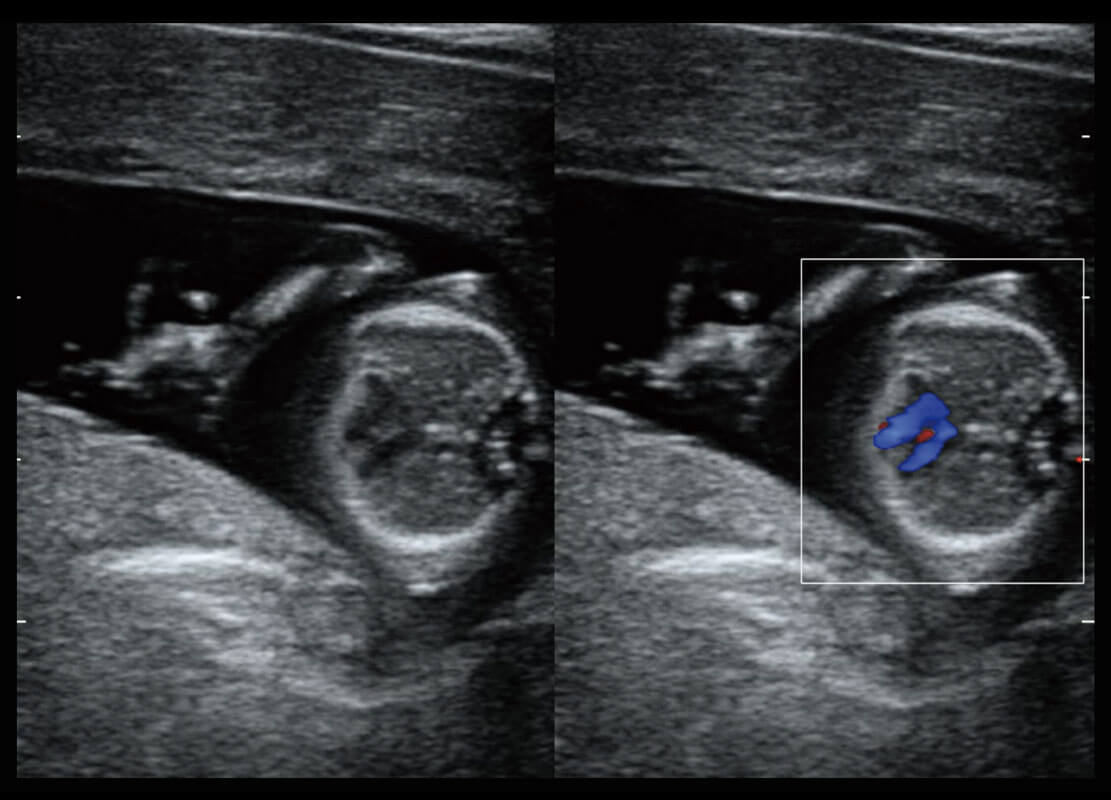

早孕-胎心

高分辨率容积成像-早孕胎儿